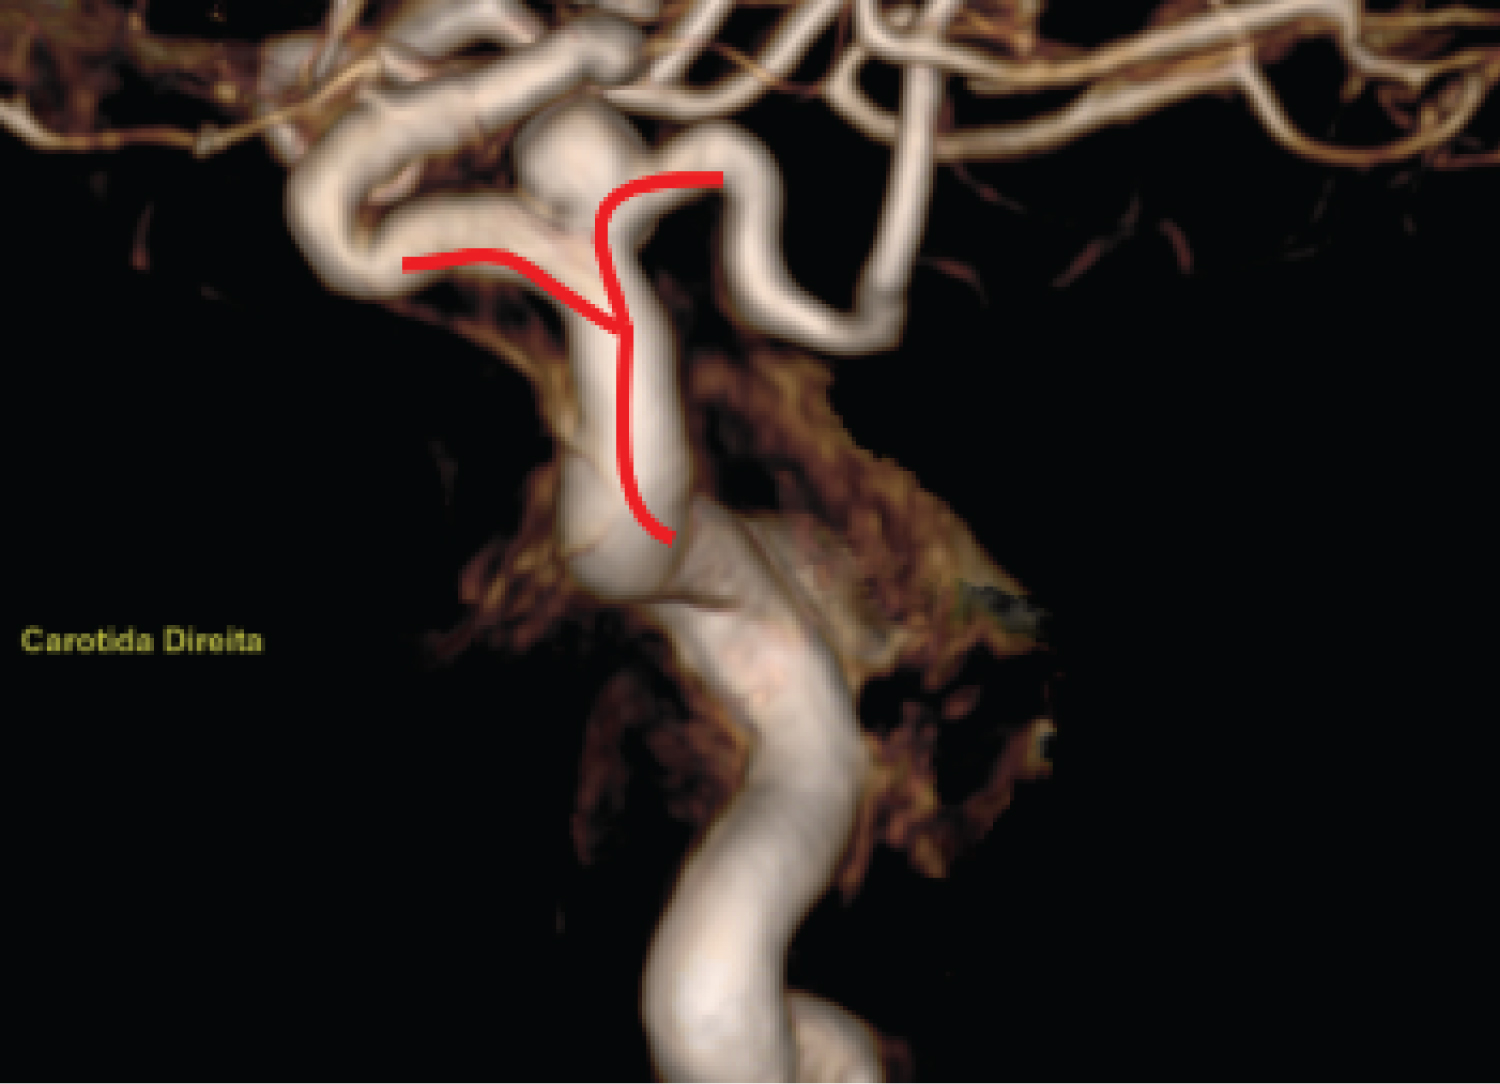

The diagnostic workup was extended with cerebral arteriography, during which the trident sign (Figure 2) compatible with Persistent Trigeminal Artery was observed, along with the absence of the right posterior communicating artery (P-com), classifying the Persistent Primitive Trigeminal Artery as type I of Saltzman. The left P-com originates from fetal circulation (Figure 3), while the right vertebral artery terminates in the right Posterior Inferior Cerebellar Artery (PICA), and the left vertebral artery is dominant (Figure 4).

Figure 2: Arteriography of the right internal carotid artery (RICA), arterial phase, with 3D reconstruction showing the trident sign (red). View Figure 2